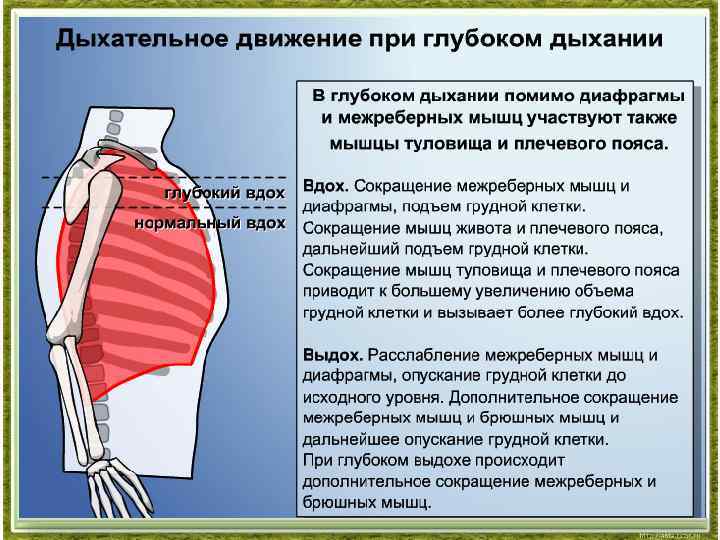

При любом типе дыхания за обработку кислорода отвечают легкие. Но их увеличение, как и изменение объема полости груди, зависит от 2 разных способов:

- При вдохе стенка груди приподнимается и отодвигается от позвоночника, из-за чего полость грудной клетки спереди увеличивается (образуется дополнительный объем между позвоночником и грудиной). В этом процессе участвуют ребра, прикрепленные к позвоночнику под острым углом. Своими концами они формируют дугу, расширяя возможный объем. Так как ребра крепятся к грудной кости, они тянут ее за собой.

- Второй способ зависит от опущения грудобрюшной преграды по направлению книзу. Это – диафрагма, имеющая куполообразную форму. Грудные мышцы отвечают в процессе дыхания за то, чтобы этот купол тянулся вниз, освобождая простор для легких. Середина опускается книзу и создается нужный объем. Из-за опущения грудная часть диафрагмы давит на живот, в результате выпячивается его стенка.